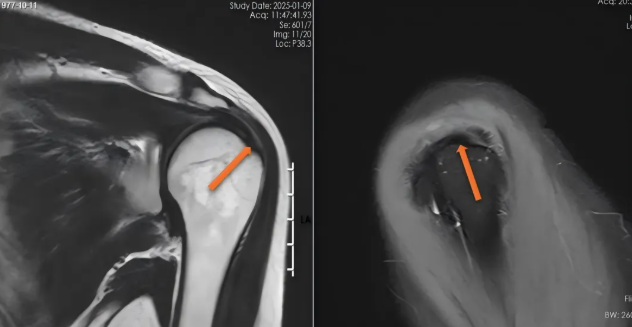

肩袖由冈上肌、冈下肌、肩胛下肌和小圆肌的肌腱共同构成,形似袖套包裹肱骨头。正常情况下,肌腱在MRI图像上呈现为均匀的低信号(黑色)。当发生损伤时,可能表现为肌腱增粗、连续性中断、信号异常,在压脂序列上信号增高(白色)。

图1-2.正常肌腱表现为黑色(橙色箭头所示)